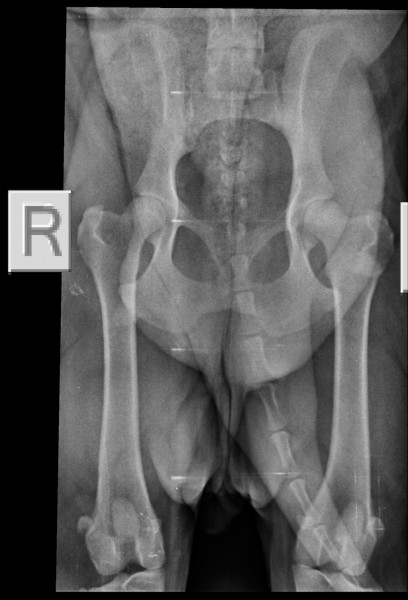

HD-A, ED-0/0